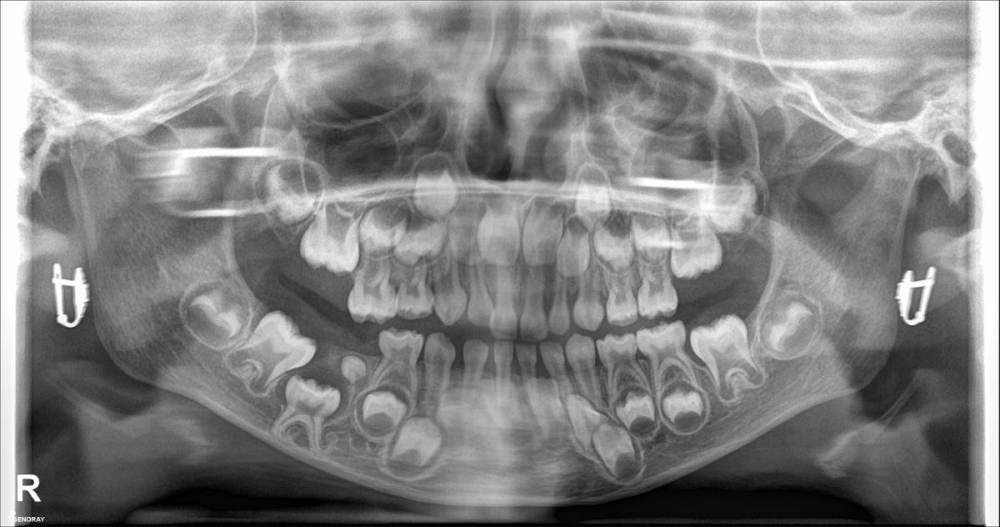

Maaamy Опубликовано 21 июня, 2022 Поделиться Опубликовано 21 июня, 2022 Здравствуйте. У ребенка 4,9 л. не прорезался молочный зуб. На рентгене видно, что есть компонент, который или мешает или мешал прорезыванию. Помогите определиться с дальнейшей тактикой диагностики и лечения. Также имеется перекрестный прикус. У местных стоматологов мнения разделились между удалять этот маленький компонент и скорее всего "засевший" молочный зуб или пока наблюдать. Что бы предложили Вы, и если операция, то какая и какие перспективы по нормальному строению челюсти в дальнейшем? Заранее спасибо Ссылка на комментарий

CRAZYDUCK Опубликовано 21 июня, 2022 Поделиться Опубликовано 21 июня, 2022 Направить на кт этой зоны ( визуализировать «образование», понять с чем имеете дело , двухмерного снимка недостаточно . удалять 8.5 однозначно , это анкилоз . Удаление в условиях общего обезболивания ( наркоз ). 8.5 анкилозирован, в таком случае этот зуб не даёт нормально развиваться участку челюсти . Это уже видно на снимке - обратите внимание на продольную ось 4.6 , она наклоняется в сторону анкилоза . Сравните с нормальной стороной 3.6 зуб . Удалить в плановом порядке , из-за сложности предстоящего удаления - челюстной лицевой хирург , работающий с детьми . 1 1 Ссылка на комментарий

CRAZYDUCK Опубликовано 21 июня, 2022 Поделиться Опубликовано 21 июня, 2022 После удаления анкилозировпнного зуба рост нормализуется , но 8.5 очень низко и толщина челюсти в этой зоне маленькая , поэтому удаление должен делать доктор с опытом ведения детей в похожих ситуациях 1 1 Ссылка на комментарий

CRAZYDUCK Опубликовано 21 июня, 2022 Поделиться Опубликовано 21 июня, 2022 После восстановления понадобится помощь врача ортодонта , профилактика смещения зуба 4.6 вперёд . зону нижних передних зубов тоже наблюдать ( обвела красным ) у ортодонта я думала вопрос задаёт врач . Поэтому отвечала таким языком . Сейчас нарисую на вашем снимке для наглядности 1 1 Ссылка на комментарий

CRAZYDUCK Опубликовано 21 июня, 2022 Поделиться Опубликовано 21 июня, 2022 Только что, Maaamy сказал: Здравствуйте. Я правильно понял ,что анкилоз - это сращивание невылезшего молочного зуба с костной тканью (погуглил)? Есть ли хоть какая-то вероятность, что если удалить эту лишнюю маленькую"бубочку", то пятерка попрёт вверх со временем, с учётом того, что челюсть будет расти? Не попрет , «бубочка» не является причиной анкилоза и ее удаление не будет влиять на нормализацию роста челюсти в этой зоне . эта бубочка , вероятнее всего зачаток постоянного , который должен быть под зубом 8.5 . Но что-то «пошло» не так как нужно 1 Ссылка на комментарий